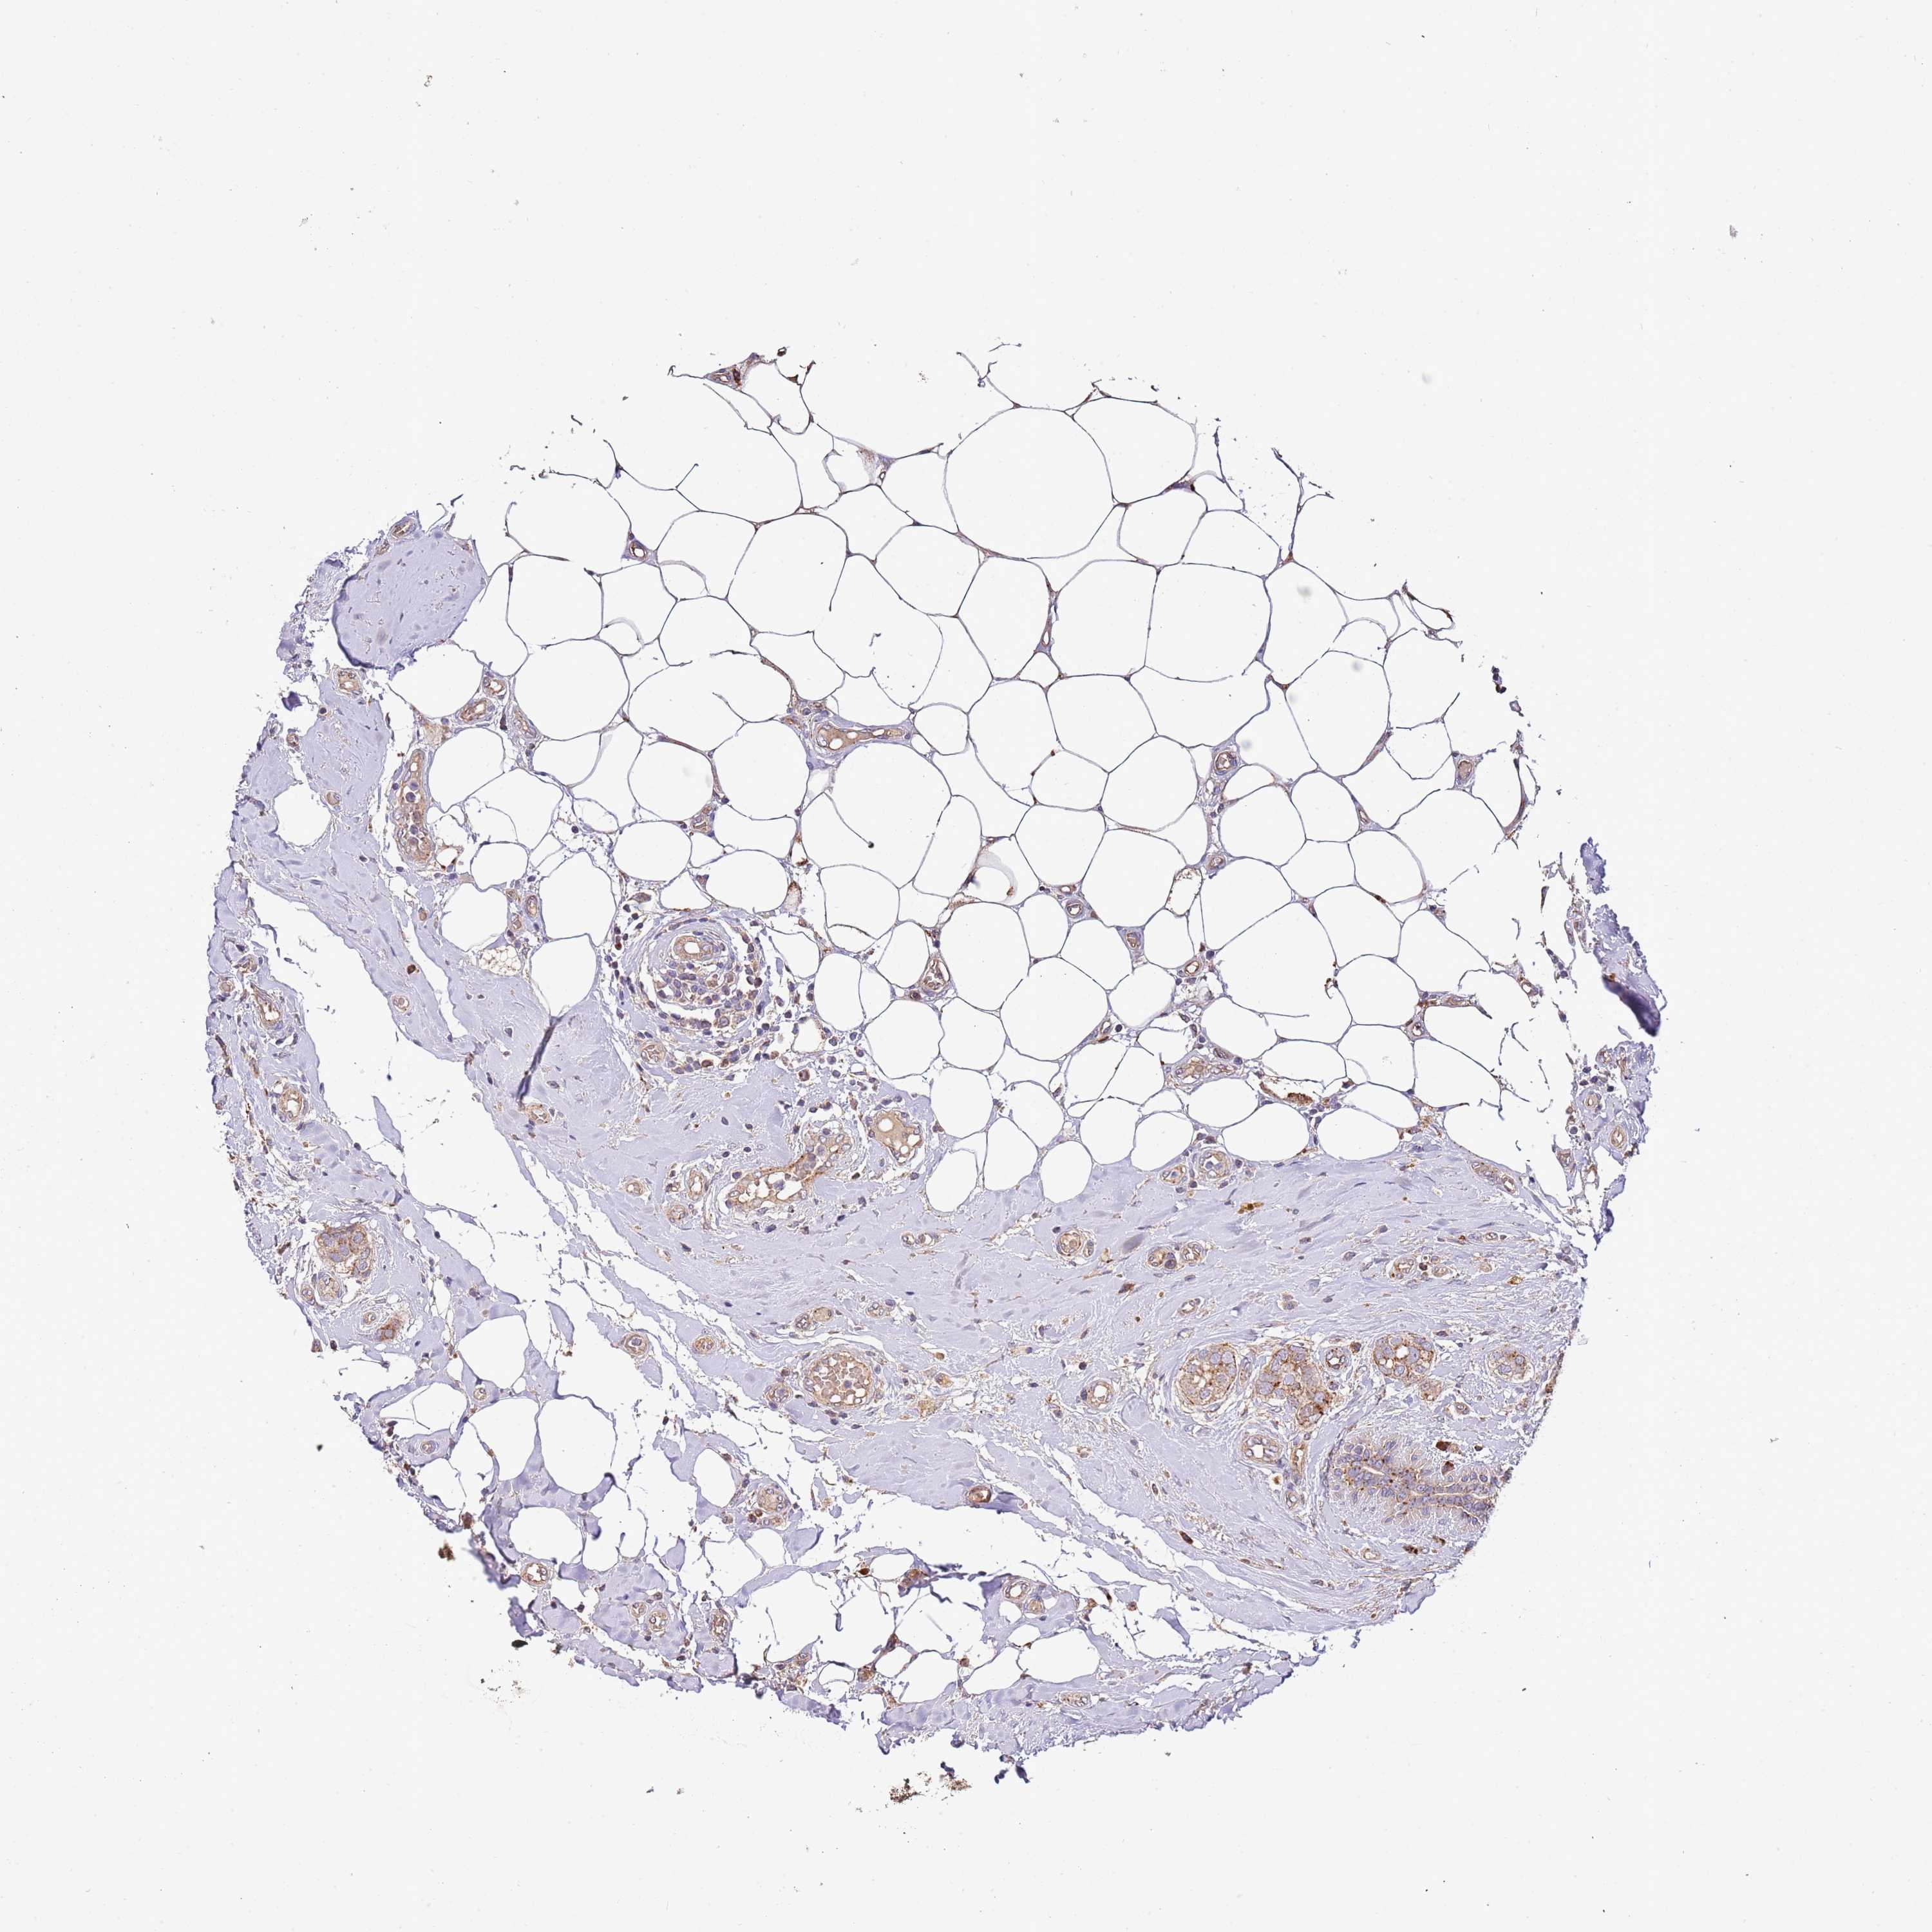

CANCER BREAST CANCER Show tissue menu

BRCA TCGA BRCA VALIDATION PROTEIN EXPRESSION